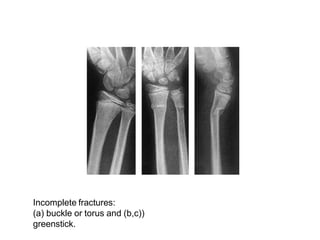

Incomplete fracture

• The bone is incompletely divided and

the periosteum remains in continuity

• Greenstick fracture : bone is buckled or bent

– Mainly seen in children, because of their

springy bones

– Plastically deformed bones

• Compressed fracture: crumpled cancellous

bone

– Seen in adults, mainly in vertebral bodies,

calcaneum and tibial plateu

Incomplete fractures:

(a) buckle or torus and (b,c))

greenstick.